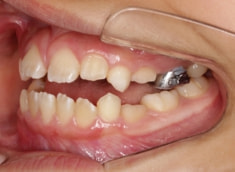

治療開始時